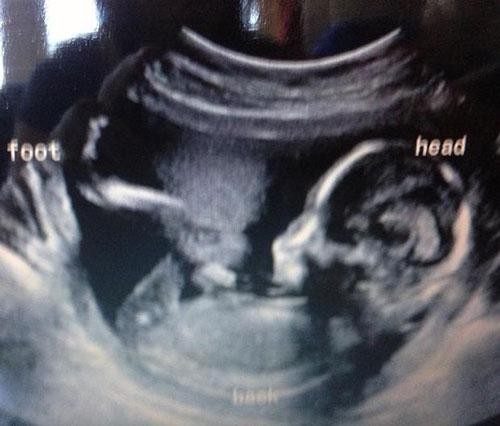

Allah anne ve babasına dayanma gücü versin... bebeklerinin cinsiyetlerini öğrenmek istediler ama...

Bebeklerinin bu ilk görüntüsüyle anne-babalar şoke oldu!